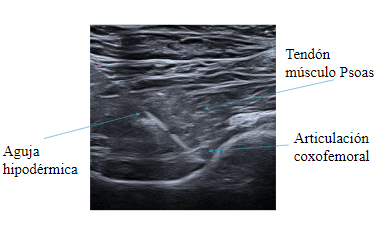

La infiltración ecoguiada es un procedimiento médico avanzado y mínimamente invasivo que utiliza el ecógrafo (ultrasonido) para inyectar medicamentos con precisión milimétrica directamente en la estructura dañada (articulaciones, tendones, músculos o ligamentos). Al visualizar el tejido en tiempo real, se garantiza que la sustancia llegue al objetivo sin dañar estructuras nerviosas o vasculares cercanas.

Se realiza en consulta, es rápido, apenas doloroso y permite un alivio rápido del dolor con menos efectos secundarios sistémicos al ser local.

Mayor precisión y eficacia: A diferencia de las infiltraciones "a ciegas", esta técnica asegura el depósito exacto del fármaco, aumentando la eficacia del tratamiento.

Seguridad: Reduce el riesgo de complicaciones, ya que el especialista ve la aguja en tiempo real y evita estructuras nobles.